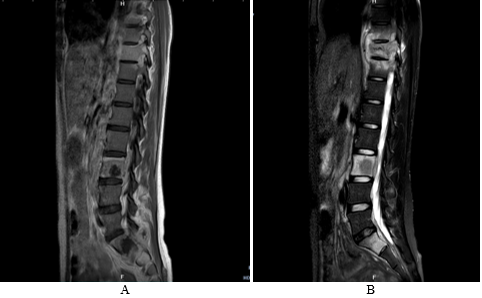

The chest X-Ray showed an enlargement of the middle mediastinum associated to pleural effusion opacity, but any active pulmonary lesions (Figure 1). A computed chest tomography revealed the presence of a parietal mass centered on the sternum, with extension in the soft parts, bone lies of the sternal manubrium, lies of the vertebral hemi-bodies of T10 and T11, cervical lymph nodes, phrenic mediastinal and sub-pectoral nodes with peritoneal and mesenteric involvement (Figure 2). Magnetic resonance imaging of the spine showed tiered thoracic lumbar and sacral spondylitis with paravertebral and anterior epidural collections responsible for spinal cord compression next D10 without signs of spinal cord pain (Figure 3).

Figure 1 Chest X-ray showing an enlargement of the middle mediastinum associated to a pleural effusion opacity.